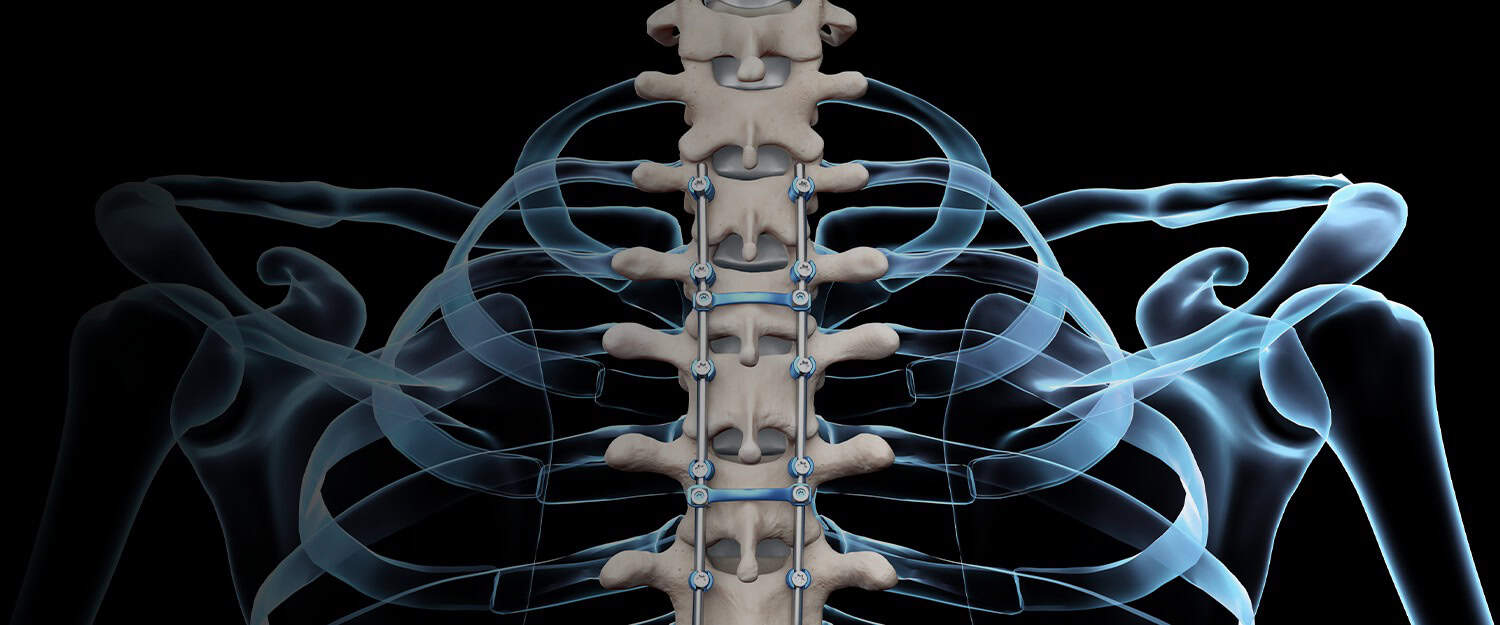

Posterior Spinal Fusion (PSF) is a surgical procedure designed to correct and stabilize the spine. It utilizes screws and rods, along with bone grafts, to help the treated vertebrae gradually unite into a single solid segment. This process helps prevent further deterioration in the fused area of the spine.

- Stabilizing the correction using implants, such as rods and screws.

- Pedicle screws are inserted into selected vertebrae.

- Rods are attached to correct and stabilize the spinal curve.

- Bone graft is applied to support the fusion process.